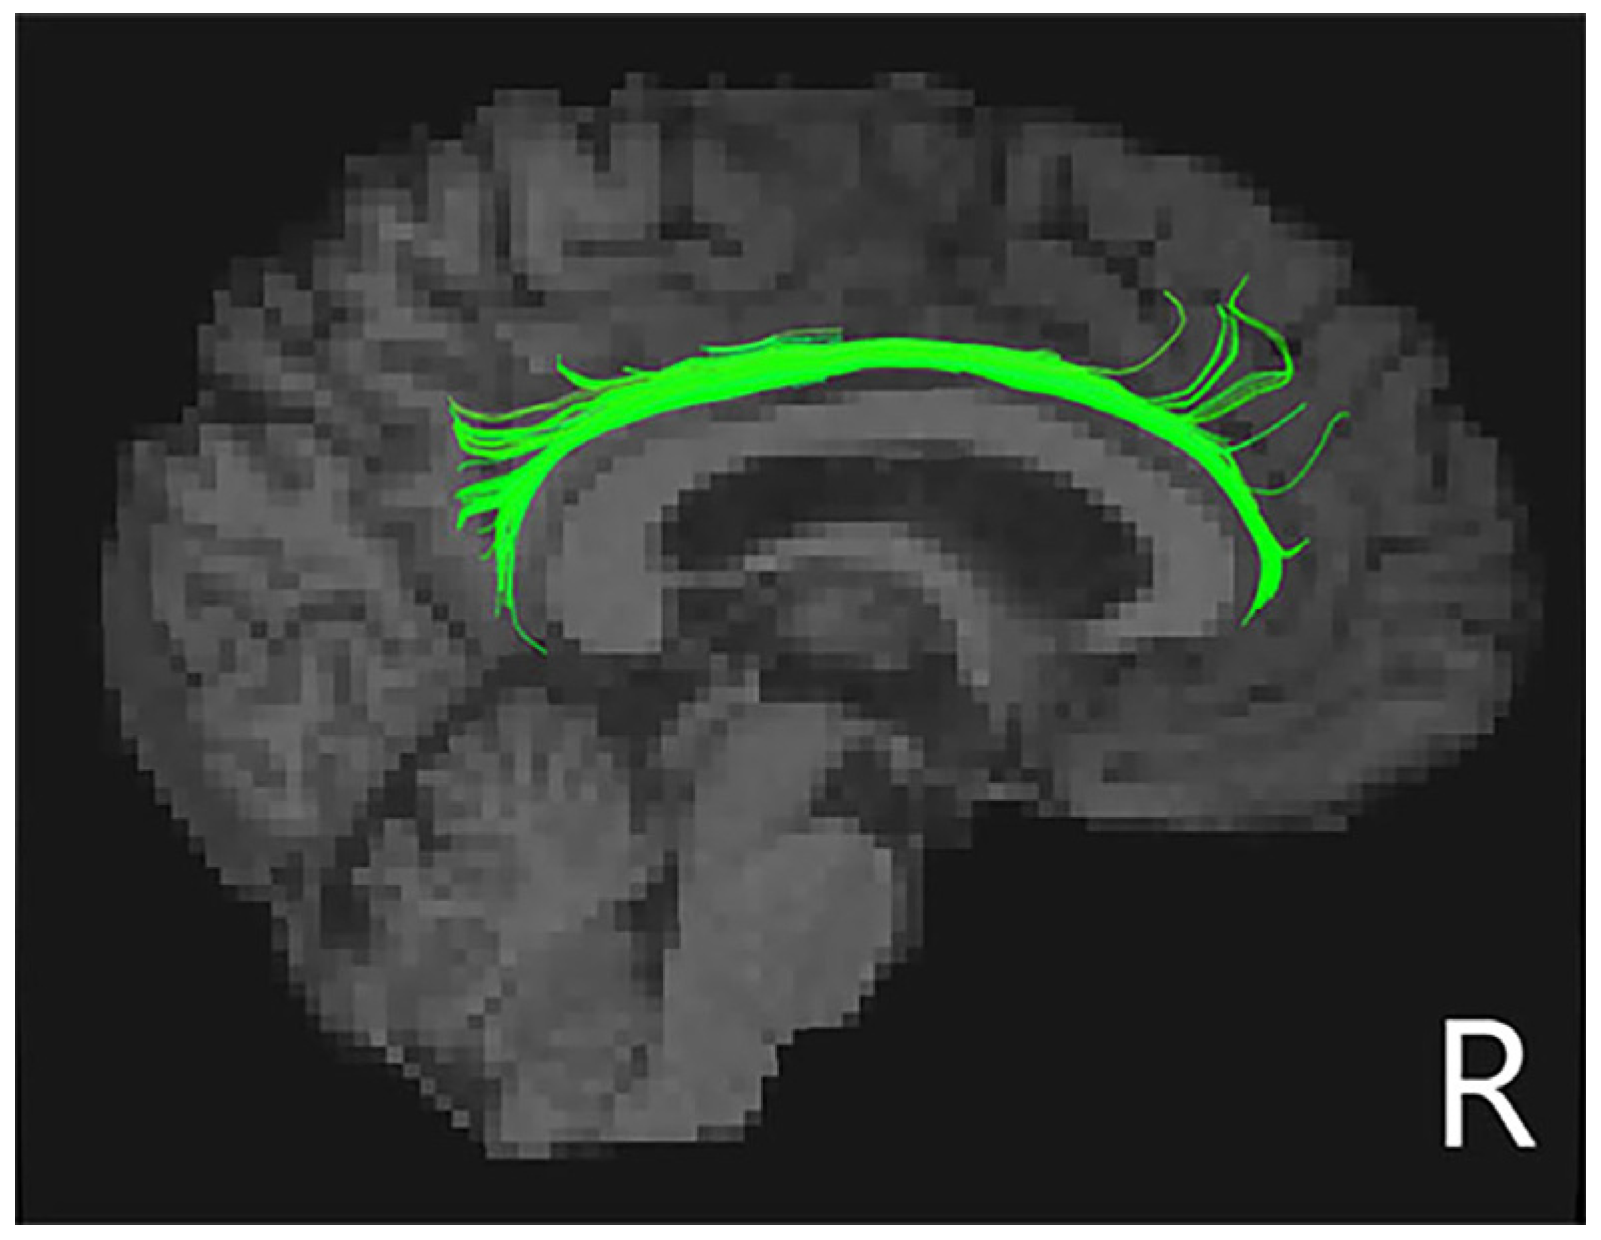

3.3. White Matter Tracts

| Tract | PD-No-Punding (n = 19) | PD-Punding (n = 19) | p-Value | |

|---|---|---|---|---|

| FA | R_CCing | 0.500 ± 0.027 | 0.470 ± 0.026 | 0.006 * |

| MD (×10−3 mm2 s−1) | R_CCing | 0.692 ± 0.032 | 0.720 ± 0.041 | 0.038 a |